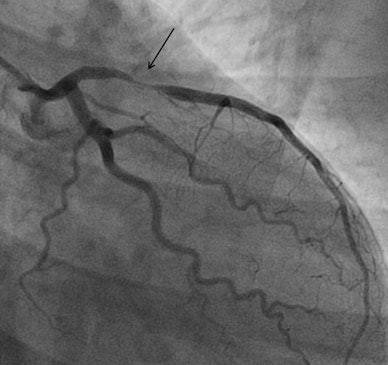

A total of 106 patients (41.2%) had a positive stress echo, and 61 underwent invasive angiography, in which 15 (24.6%) were revascularized. The average cost per patient for all studies was 654 pounds (748 euros). If NICE guidance had been followed, the costs would have been significantly higher at 1,400 pounds (1,602 euros), a difference of 746 pounds (853 euros).

"Our registry of 257 patients demonstrates that stress echo is clinically effective, reduces the cost of investigations by reducing the need for invasive coronary angiography, and appears to be safe with only two myocardial infarctions recorded in a 12-month period, both in patients with a positive stress echocardiogram," Papachristidis told AuntMinnieEurope.com.

There will certainly be false-negative tests with initial noninvasive tests, and CCTA does a good job as well -- with an initial sensitivity of 81% and a negative predictive value of almost 97%, they noted. But the CCTA-first strategy has been criticized. Moreover, for patients with high pretest probabilities, a negative noninvasive test may not be able to conclusively rule out coronary disease. Yet, noninvasive tests are attractive because they can reduce complications, are widely available, and can reduce the time to diagnosis, the study team noted.